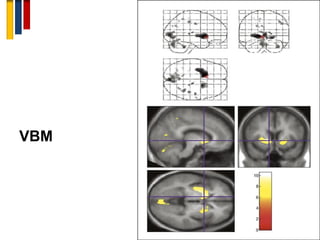

9. Voxel-based morphometry (VBM)

• Voxel-based morphometric (VBM) analysis is an accurate

quantification of GM atrophy on a voxel-by-voxel basis.

VBM